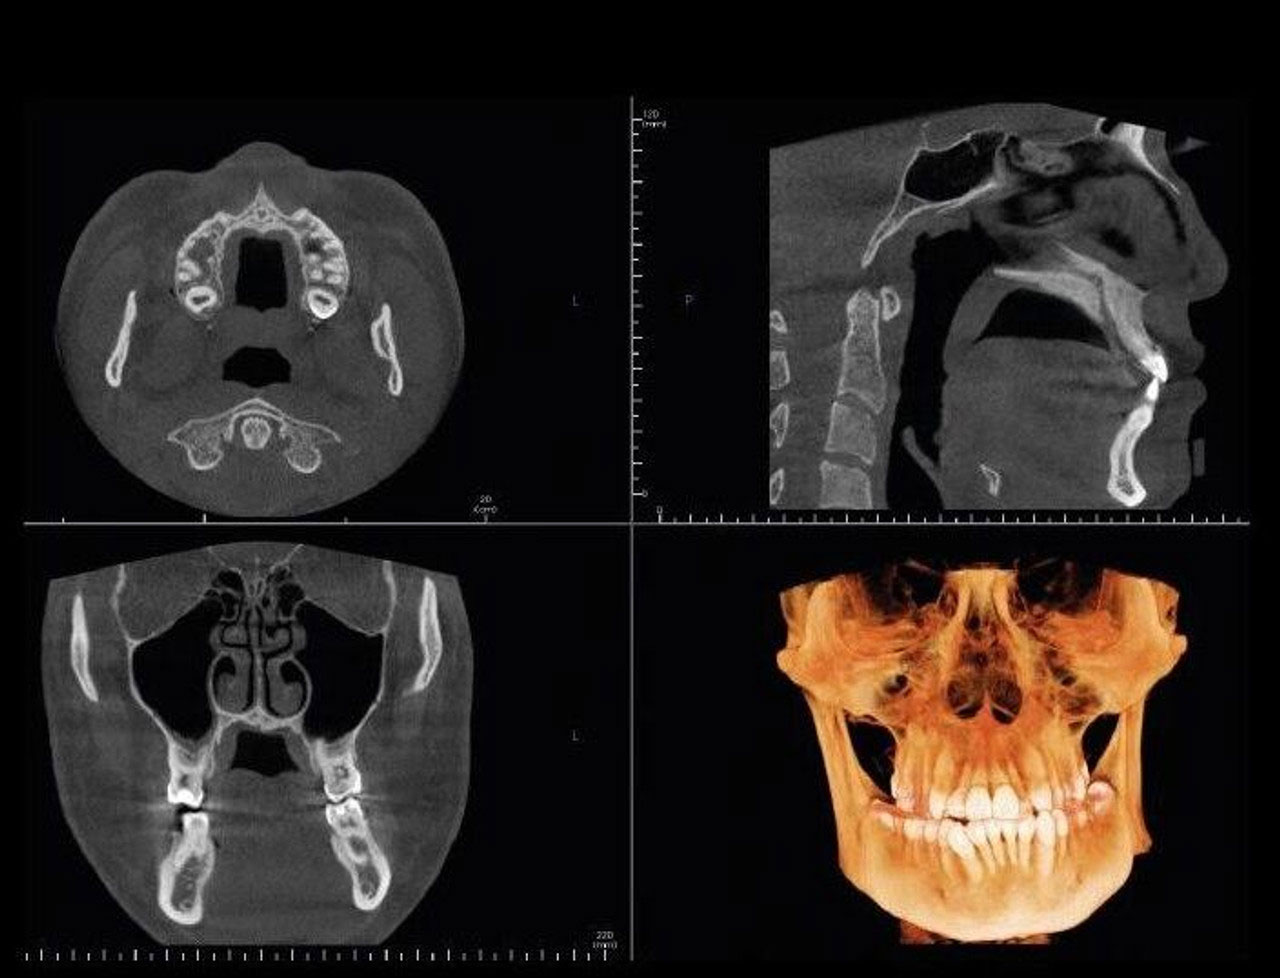

CBCT (Cone Beam Computed Tomography) ist eine dreidimensionale Aufnahme, auf der alle Details sichtbar sind (insbesondere das Knochenvolumen für die Oralchirurgie und die Implantation, die Diagnose für Erstuntersuchungen, Entzündungszustände, Wurzelkanalbehandlungen usw.) (link na Popravak i liječenje zuba/Zahnreparatur)

Heutzutage ist die dreidimensionale Aufnahme der Standard, da wir alle Zweifel beseitigen möchten. Darauf sind alle Informationen sichtbar, die wir für eine qualitativ hochwertige Diagnosestellung und Therapieplanung benötigen.

Es ist möglich, folgende 3D-Aufnahmen zu erstellen:

- eines Kieferabschnittes– kleines Feld

- beider Kiefern – mittleres Feld

- des Oberkiefers und des Jochbogens – großes Feld.